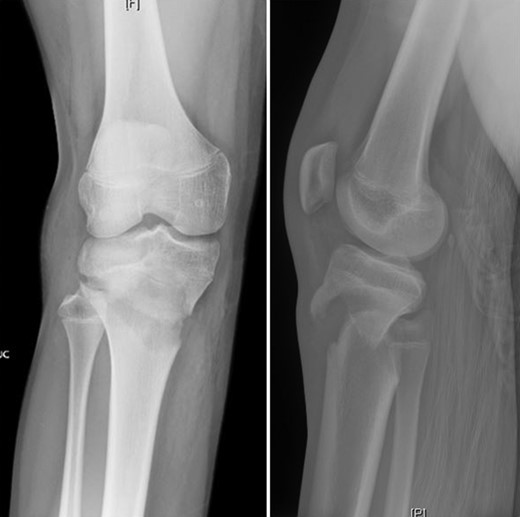

Patient is a 14-year-old male who slipped and fell while jumping off of a diving board and landed onto a flexed right knee. The patient was stable on presentation and neurovascularly intact with the knee locked in flexion. Skin was tenting anteriorly over the tibial tubercle and his compartments were swollen but compressible. A single plain film view (Fig. 1) was obtained prior to orthopaedic consultation. Closed reduction under sedation and splitting was attempted in the ED with partial but unsatisfactory improvement. Post-reduction radiographs (Fig. 2) demonstrated a tibial tubercle fracture with extension through the entire proximal tibial physis with metaphyseal involvement posteromedially. We classified this as a type IV tibial tubercle fracture, Salter–Harris II variant. In conjunction with patient and family we planned for urgent closed versus open reduction and application of knee-spanning external fixator. Immediately prior to surgery in the pre-operative holding area, the patient noted increasing right leg pain. In the operating room (OR), a marked increase in swelling with tense skin was observed. Due to rapidly progressive swelling and nature of the fracture, the decision was made to proceed with a 4-compartment fasciotomy of the right leg. The medial-sided fasciotomy (Fig. 3) revealed significant bulging of the superficial and deep compartments; however, the anterior and lateral compartments were less swollen. The fracture was unable to be closed reduced intraoperatively, therefore proximal extension of the medial fasciotomy wound was performed to open and reduce the fracture under direct visualization. Anatomic reduction was achieved and a knee-spanning external fixator was applied (Fig. 4). Approximately 72 hours later the patient was brought back to the OR for irrigation and debridement, lateral wound closure, and medial wound vacuum placement. Another 72 hours later, he returned to the OR for removal of the external fixator, ORIF, and split-thickness skin grafting of the medial fasciotomy site. An anterolateral approach was used with a 3.5 mm proximal tibial locking plate (Fig. 5). At most recent follow-up (Fig. 6), six months post-op, the patient is pain free, ambulating without assistive device, and has returned to all desired activities.

AP and lateral radiographs after attempted closed reduction which reveal type IV tibial tubercle fracture with posteromedial metaphyseal extension (Salter–Harris II variant).